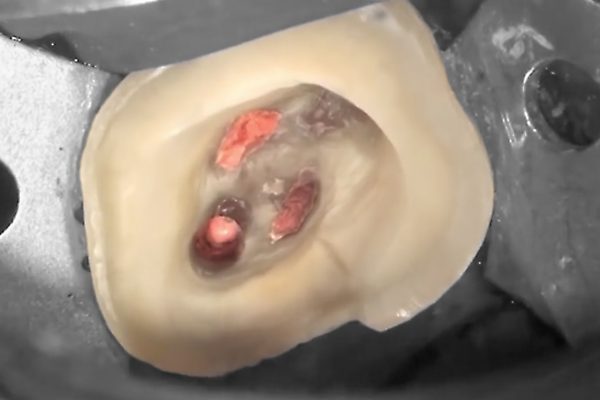

- Dentisteria: tratamento de cáries e de fracturas dentárias com restaurações estéticas e branqueamento dentário:

- Endodontia: desvitalização de dentes infectados, com fracturas ou cáries extensas;